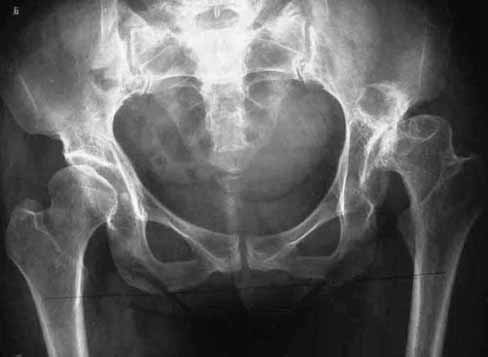

34岁女性,先天髋脱位,骨关节炎,疼痛严重.

术前常规行骨盆、股骨上段X线片及髋关节CT检查确定造臼部位和臼壁厚度,并根据髋关节假体模板确定股骨矩保留长度及骨髓腔尺寸.